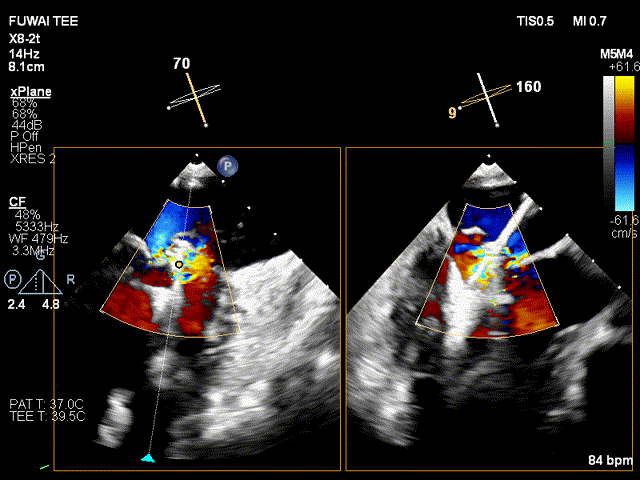

手术团队使用MitraClip®独特的三层双调弯导管,经股静脉穿刺,在食道超声引导下完成房间隔穿刺。穿刺后将导管送入左心房,对准二尖瓣目标位置P2区域。准确捕捉瓣叶,二尖瓣夹释放后,超声显示反流几近消失,患者各项生理指标正常,手术顺利完成。